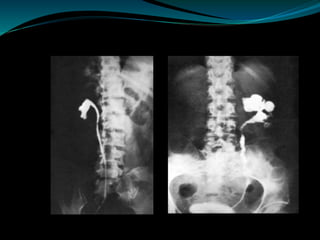

Intravenous Urography (IVU)

 The most common findings being hydrocalycosis,

hydronephrosis, or hydroureter due to stricture formation.

 Early signs include the moth-eaten appearance of calyceal

erosion and papillary irregularity. These signs are best seen on

early excretory films.

 Calyceal obliteration and amputation, hydrocalycosis,

segmental or total hydronephrosis, and a s reduced capacity

renal pelvis may all be signs of renal tuberculosis .

Ureter and Bladder

 Scarring and angulation of the ureteropelvic junction

(UPJ) may also occur, the so-called “Kerr’s kink”.

 Tuberculosis of the ureter is commonly seen as a rigid,

straightened “pipe-stem” ureter. A beaded, corkscrew

appearance is sometimes also seen.

 Ureterovesical junction obstruction is caused by

tuberculous cystitis or strictures of the distal third of

the ureter.

 The cystogram films may show a small contracted

bladder due to excessive fibrosis (thimble bladder).

 Thimble or systolic bladder – inability to relax and

distend (capacity <100ml)

IVU of ureter and bladder